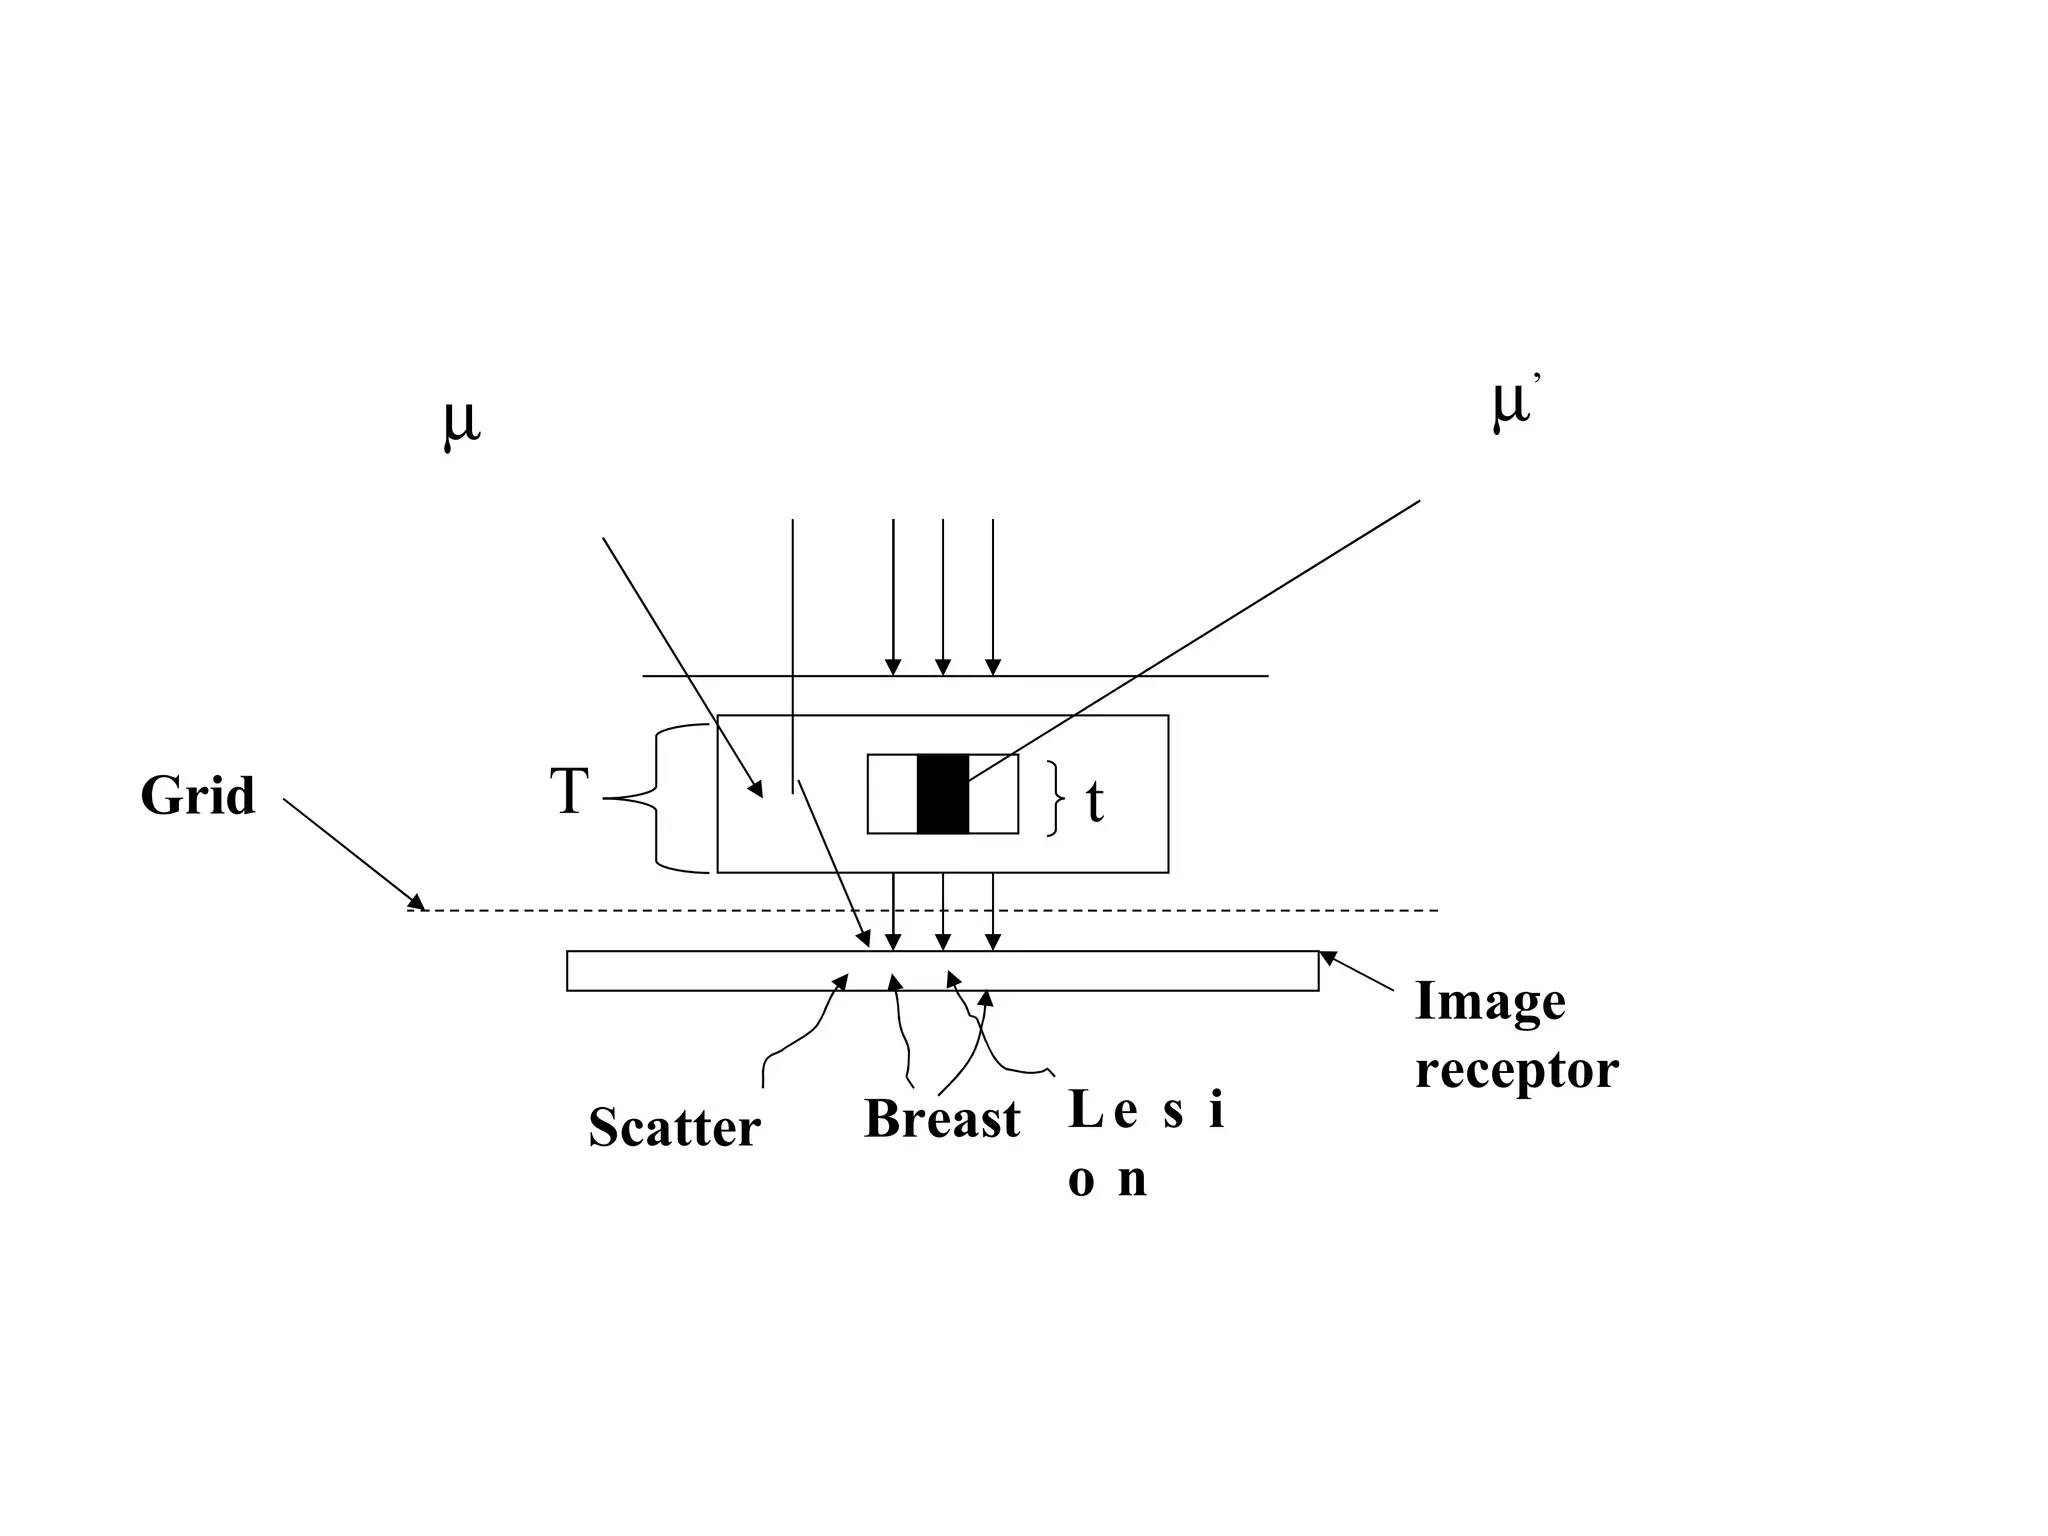

The document discusses various medical imaging modalities including x-rays, computed tomography (CT), and digital mammography. It describes the basic principles and historical development of these technologies, how images are formed, and what types of anatomical features and abnormalities they can detect. Key advances include the development of digital systems that allow image manipulation and remote consultation. While promising, digital mammography still faces challenges around resolution and cost.